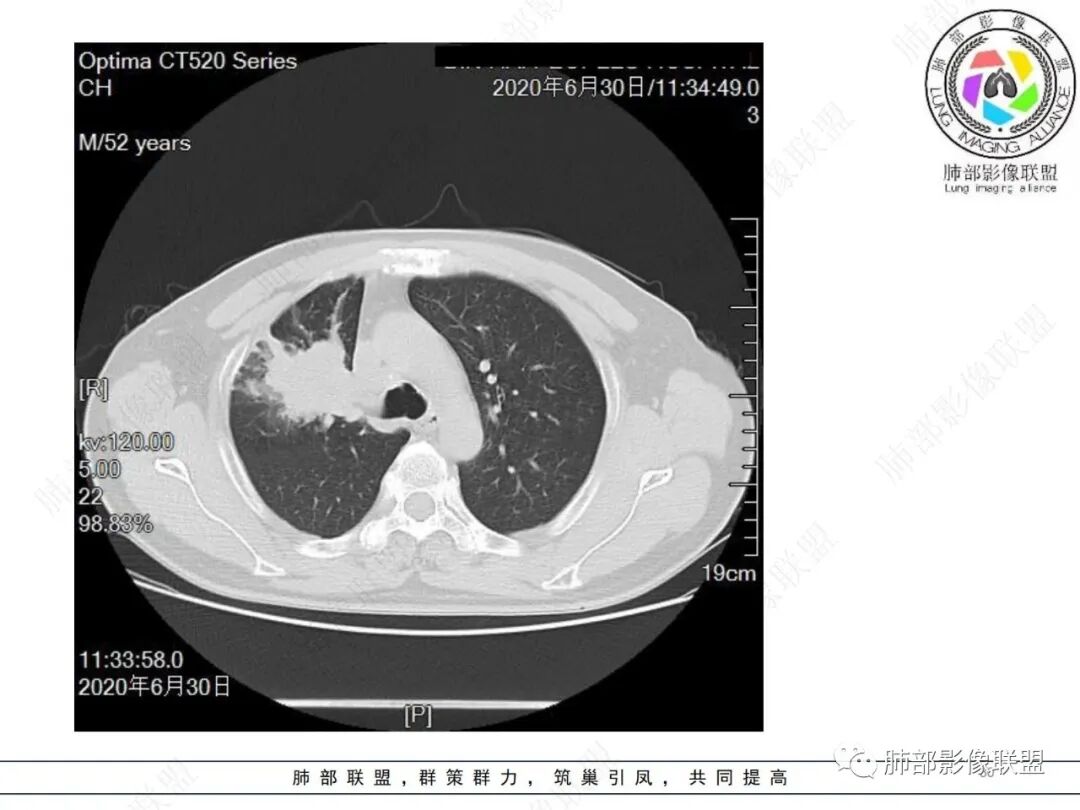

中年男性,有长期吸烟史,右肺上叶不规则肿块,边缘膨隆有分叶,支气管截断,不均匀强化,内有多灶性坏死,癌胚抗原升高,考虑肺癌可能性大,鳞癌可能。鉴别腺癌。

右肺上叶不规则形软组织密度肿块影,边缘见分叶,毛刺,病灶呈宽基底与胸膜相连,病灶内见坏死,增强扫描呈不均匀性强化,右肺上叶支气管截断,纵隔内见肿大淋巴结,肿瘤标志物增高,考虑鳞癌可能,鉴别小细胞癌,腺癌。

老年人,右肺上叶肺不张伴阻塞性炎症,右肺上叶支气管闭塞,增强病灶强化不均匀,可见边缘不清晰的坏死,纵膈淋巴结增大,考虑中央型肺癌,鳞癌可能性大。

右肺上叶不规则肿块,分叶、毛刺,上叶支气管截断,断端圆钝,不均匀强化,其内空泡及坏死,坏死边界不清,考虑腺癌或腺鳞癌,鉴别鳞癌

右肺上叶团块影,边缘膨隆,支气管近端截断,肿块内密度不均匀,见片状坏死,边界不清,纵隔肿大淋巴结,CEA明显增高,考虑恶性,鳞癌?腺鳞癌?

中年男性,长期吸烟,CT示右肺上叶肿块影,有分叶,毛刺,胸膜牵拉,支气管截断,边缘斑片影,病变内有坏死,强化,淋巴结肿大,首先考虑鳞癌可能性大,鉴别腺鳞癌

右肺上叶占位,支气管阻塞截断,病变周围可见结节及斑片状影,密度不均,坏死边缘不清,纵隔淋巴结肿大,中年男子,吸烟史,考虑鳞癌、腺鳞癌,鉴别结核

沼泽样坏死,支气管截断,周围阻塞性炎症,并淋巴道水肿,考虑腺鳞癌,鳞癌

右上叶支气管截断呈斜坡状,不均匀强化,低密度区实质区边界不清,老年男性,长期吸烟史,考虑恶性,鳞癌首选

长期抽烟的老头,右肺上叶不规则肿块,边缘膨隆有分叶,支气管截断,不均匀强化,内有片状坏死,考虑肺癌,常规思路鳞癌可能。鉴别腺癌。

中年男性,长期吸烟,右肺上叶不规则肿块,边缘膨隆有分叶,支气管截断,不均匀强化,内有多灶性坏死,癌胚抗原升高,考虑肺癌

除了年龄,吸烟,湖泊样坏死符合鳞癌,其他都不符合,支气管截断,不在肿块中央,远处也没有明显阻塞样改变,更像爬行后截断,肿瘤标志物CEA高得厉害,其他鳞癌标志物并不高。这种坏死,低分化腺癌一样常见,强化远端也有强化,不符合鳞癌,所以我考虑低分化腺癌(伴或不伴有神经内分泌分化)或者肉瘤样癌。

边缘都是强化的肿瘤组织,鳞癌是不会这样的,符合腺癌

不符合鳞癌有四点:1,截断的支气管不在肿块中央,而是外朝内爬行(肿块外缘大于近端)2、支气管截断在前段,前段远端没有阻塞性改变。3、鳞癌是近端强化,远端为阻塞性的不强化粘液栓或明显强化的不张肺组织,这个是中间坏死,周围强化的肿瘤组织。4、肿瘤标志物CEA增高太明显,鳞癌标志物不高。